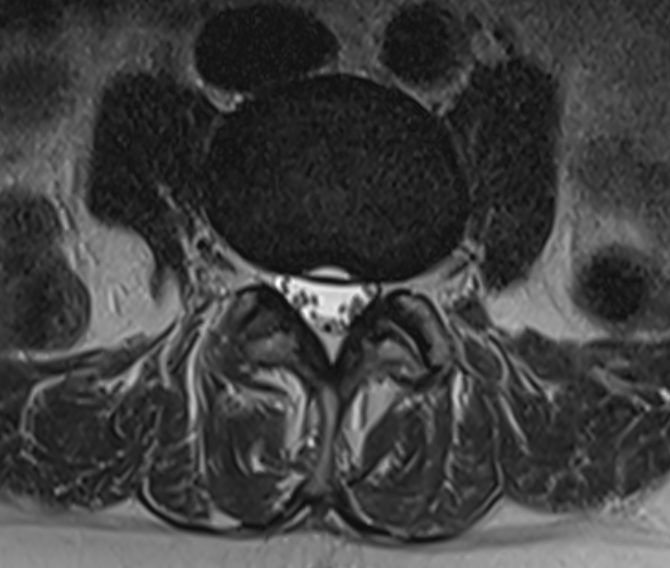

3. Transverse annulus tear of intervertebral disc